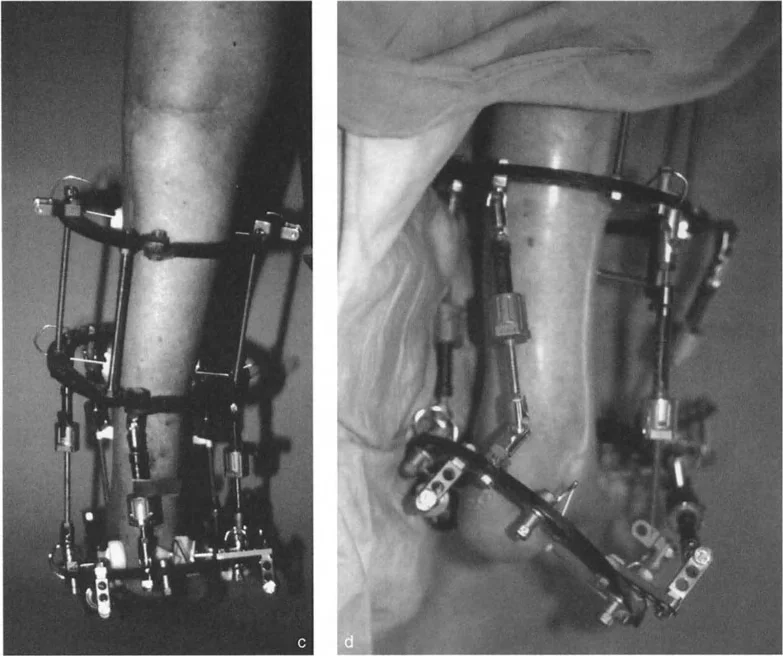

تطويل وتر العرقوب (Achilles Tendon Lengthening)

هذه العملية ضرورية عندما يكون وتر العرقوب قصيرًا ومشدودًا، مما يحد من حركة ثني القدم للأعلى.

- تطويل وتر العرقوب بالشق الجلدي (Percutaneous Z Tendo Achillis Lengthening):

- تُفضل هذه الطريقة في حالات تقوس الكاحل الناتج عن قصر وتر العرقوب فقط، لتجنب التطويل المفرط للوتر.

- يتم إجراء شقوق صغيرة في الجلد وإدخال مشرط خاص (Smillie knife) لعمل شقوق طولية وعرضية في الوتر، مما يسمح له بالتطويل التدريجي مع ثني القدم للأعلى.

- الميزة هي الحفاظ على غمد الوتر سليمًا، مما يساعد على التئام الوتر مع الحفاظ على التوتر.

إزالة النتوءات العظمية وتعميق التلم الكاحلي

في حالات تقوس الكاحل الناتجة عن اصطدام عظمي (Bony Impingement) بسبب نتوءات عظمية في حافة الظنبوب الأمامية أو في التلم الظهري لعظم الكاحل، يقوم الأستاذ الدكتور محمد هطيف بإزالة هذه النتوءات وتعميق التلم الكاحلي للسماح لعظم الكاحل بالثني للأعلى بحرية.

قطع العظم التصحيحي (Osteotomy)

عند وجود تشوهات عظمية مثل تقوس الظنبوب البعيد، قد يتطلب الأمر قطع العظم وإعادة توجيهه. على سبيل المثال، يمكن إجراء قطع عظم قبة ظهرية (Dorsiflexion focal dome osteotomy) في الظنبوب البعيد لتصحيح انحنائه.